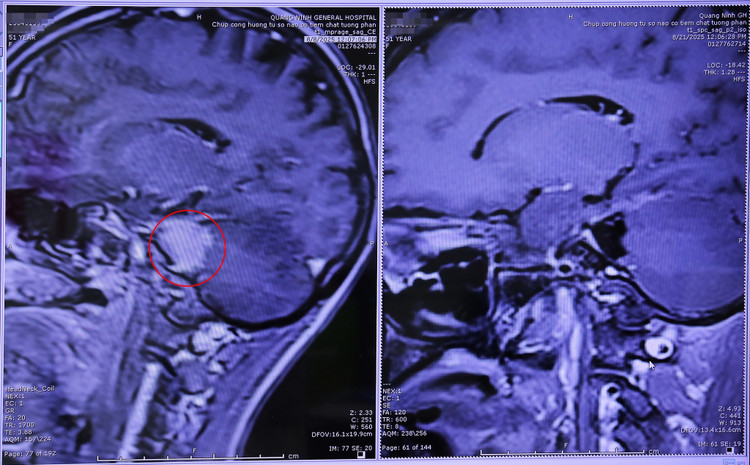

Một trường hợp khác có khối u cùng vị trí là bệnh nhân T.H.N (35 tuổi, phường Cẩm Phả, tỉnh Quảng Ninh) thường xuyên đau đầu, chóng mặt, đi lại khó khăn. Đến khám tại bệnh viện, kết quả chụp cắt lớp vi tính phát hiện 1 khối u dây thần kinh số 8 bên phải, kích thước 30x40mm, chèn ép thân não và tiểu não và các dây thần kinh sọ.

Với sự hỗ trợ của chuyên gia, kíp bác sĩ ngoại thần kinh đã thực hiện phẫu thuật lấy u thành công qua kính vi phẫu, ứng dụng hệ thống cảnh báo thần kinh trong mổ hiện đại, giúp lấy bỏ toàn bộ khối u dây thần kinh và bảo tồn cấu trúc giải phẫu các dây thần kinh.

Hình ảnh chụp cộng hưởng từ khối u dây thần kinh số 8 được phẫu thuật lấy bỏ toàn bộ - Ảnh BVCC